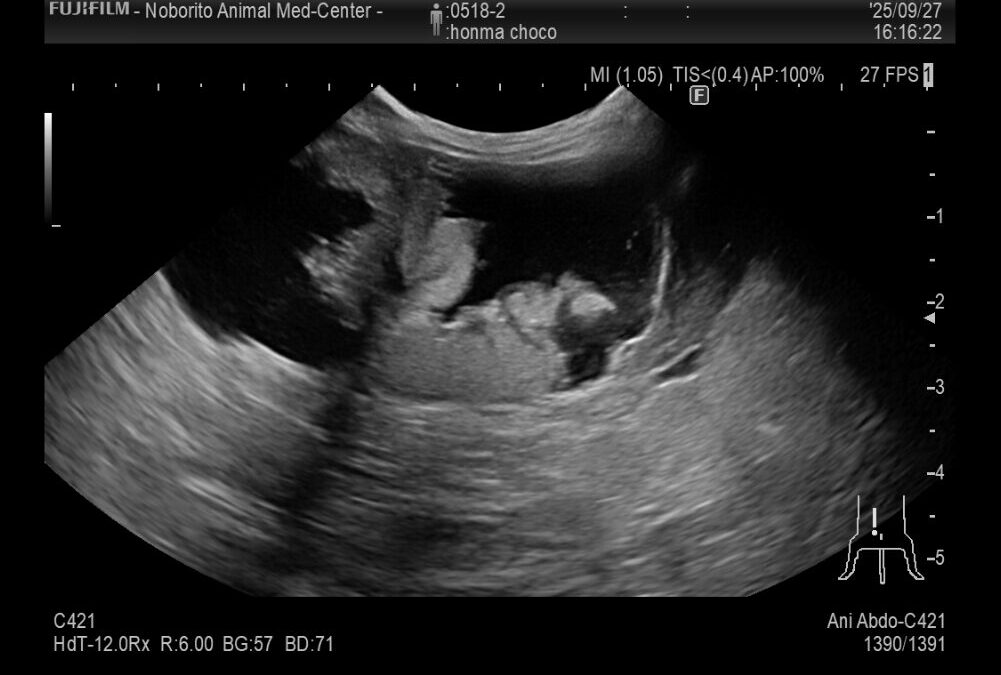

症例は8歳7ヶ月のうさぎで体調が悪い、食欲が落ちているとの主訴で来院しました。

超音波検査をしたところ子宮に水がたまっており、子宮の腫瘍が疑われたため摘出手術を行いました。

子宮は拡張しており炎症が起きていました。